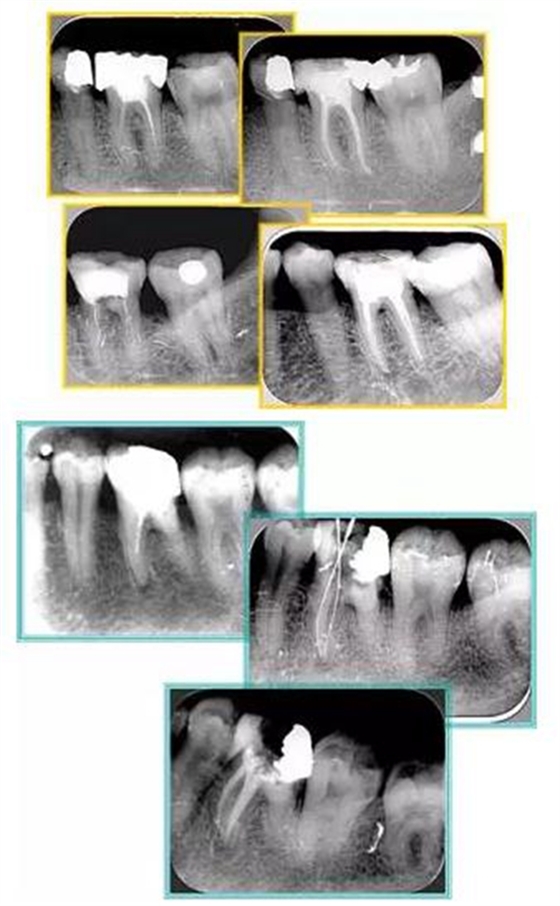

共有 4 張 X 線(xiàn)片,分別是術(shù)前、診斷絲 、主牙膠尖確認(rèn)、術(shù)后。

( 1 )術(shù)前:術(shù)前 X 線(xiàn)片用來(lái)了解牙齒的大概情況。術(shù)前預(yù)期為多根牙時(shí) X 線(xiàn)片應(yīng)偏頭拍攝。

( 2 )診斷絲:根據(jù)術(shù)前 X 線(xiàn)片進(jìn)行開(kāi)髓、根管的初步預(yù)備后,需要插入診斷絲,用來(lái)指示工作器械位置。常用 10 號(hào)或 15 號(hào)擴(kuò)大器作為診斷絲插入牙髓腔。

( 3 )主牙膠尖確認(rèn):通過(guò)術(shù)前預(yù)期和診斷絲診斷,明確工作長(zhǎng)度、牙根走向,進(jìn)行根管預(yù)備。之后應(yīng)進(jìn)行主牙膠尖(中銼)確認(rèn),已明確根管是否適合充填。

( 4 )術(shù)后:觀察治療效果。